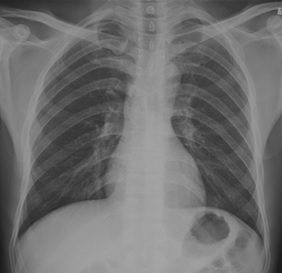

試題:根據(jù)下圖請(qǐng)做出正確診斷

A.正常胸片

B.肺門淋巴結(jié)腫大

C.肺炎

D.主動(dòng)脈型心(靴型心)

正常胸片